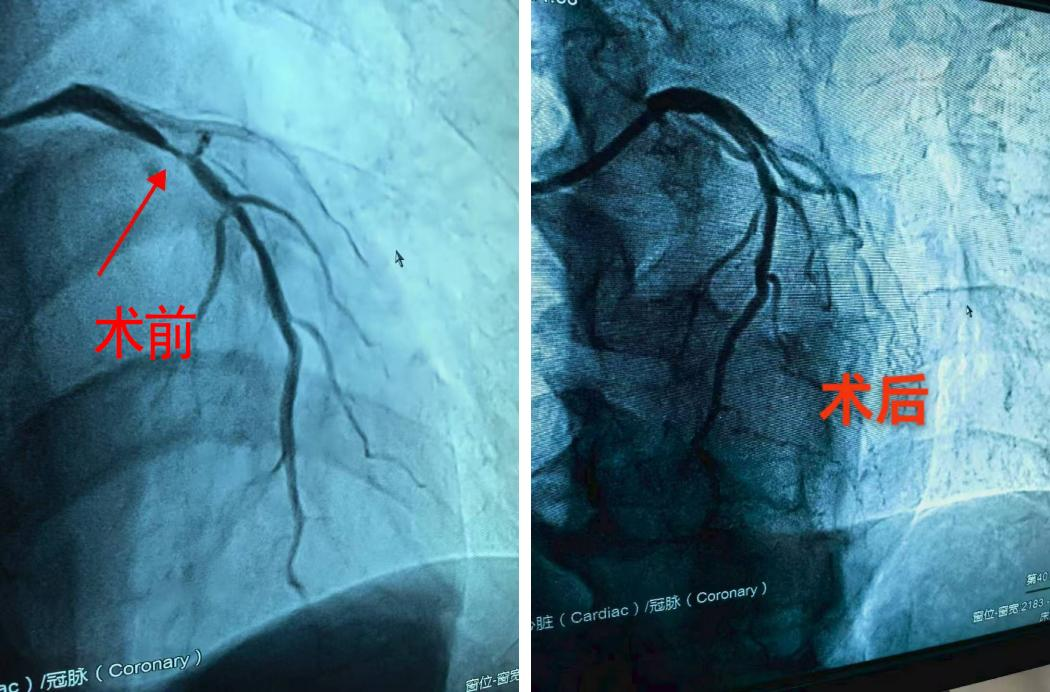

收到消息后,聂志敏通过微信交代好胸痛患者的注意事项,便立即赶回南昌市,为患者的转运和接收做好充分准备。下午5时患者到院,聂主任立刻为其安排了相关检查,经初步诊断,排除急性心梗,以“心绞痛”收治入院。在聂主任的建议下行经冠脉造影,造影结果明确显示:心脏冠状动脉前降支狭窄程度高达90%,这意味着供给心脏血液的主要通道已严重堵塞,生命随时可能受到威胁。

▲术前术后血流对比

基于准确的诊断和充分的术前准备,聂志敏当机立断,带领团队为患者实施了微创手术,送入药物球囊至病变处持续扩张,药物球囊成功打通了狭窄的血管,再次恢复血流,治疗成功!